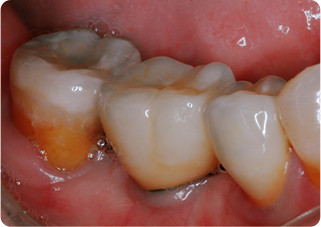

セラミックアンレー症例②

術前

むし歯除去&IDS

ラバーダム防湿

術後

| 主訴 | 右下奥歯の銀歯を白くしたい |

|---|---|

| 治療期間/回数 | 2週間、2回 |

| 価格(税込) | 143,000円(税込) |

| リスク・副作用 | セラミックの破損、一時的な知覚過敏が生じる場合がある |

| ポイント | 銀歯の中はむし歯になっていた。金属イオンにより歯の内部に黒い部分があるが、むし歯を染め出すう蝕検知液を使用し、選択的にむし歯のみを除去。また、セラミック装着時にラバーダム防湿を行うことで、詰め物の接着効果を最大限発揮できるようにした。 |